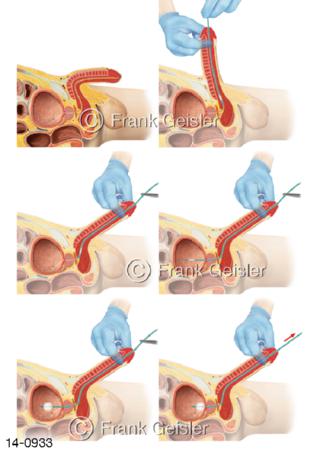

Bildergalerie Urogenitalsystem

Bilder zum Urogenitalsystem mit Urogenitalorgane, Urogenitaltrakt, zum Harn- und Geschlechtsapparat, Harnorgane und Geschlechtsorgane, Organe der Harnwege und der Fortpflanzung, Harnorgane und Geschlechtsorgane im männlichen und weiblichen Urogenitalsystem